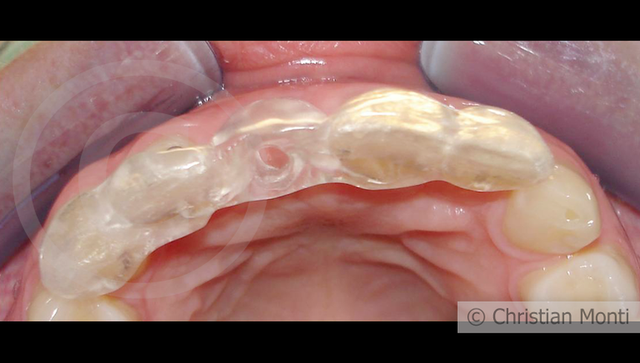

EDENTULIA SINGOLA

Impianto in sostituzione di un incisivo superiore